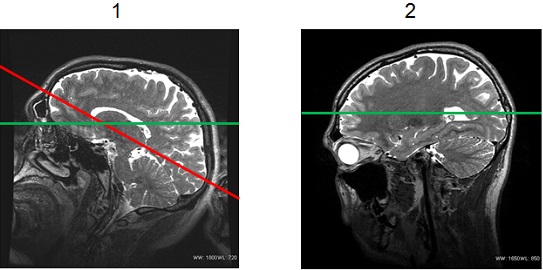

Figure 2. PROMO head position

Table 2. Image legend Number Description 1 Poor patient positioning, with the chin tilted up too far. 2 Good patient positioning. - Annotation of the rescan time is displayed on the DICOM header.